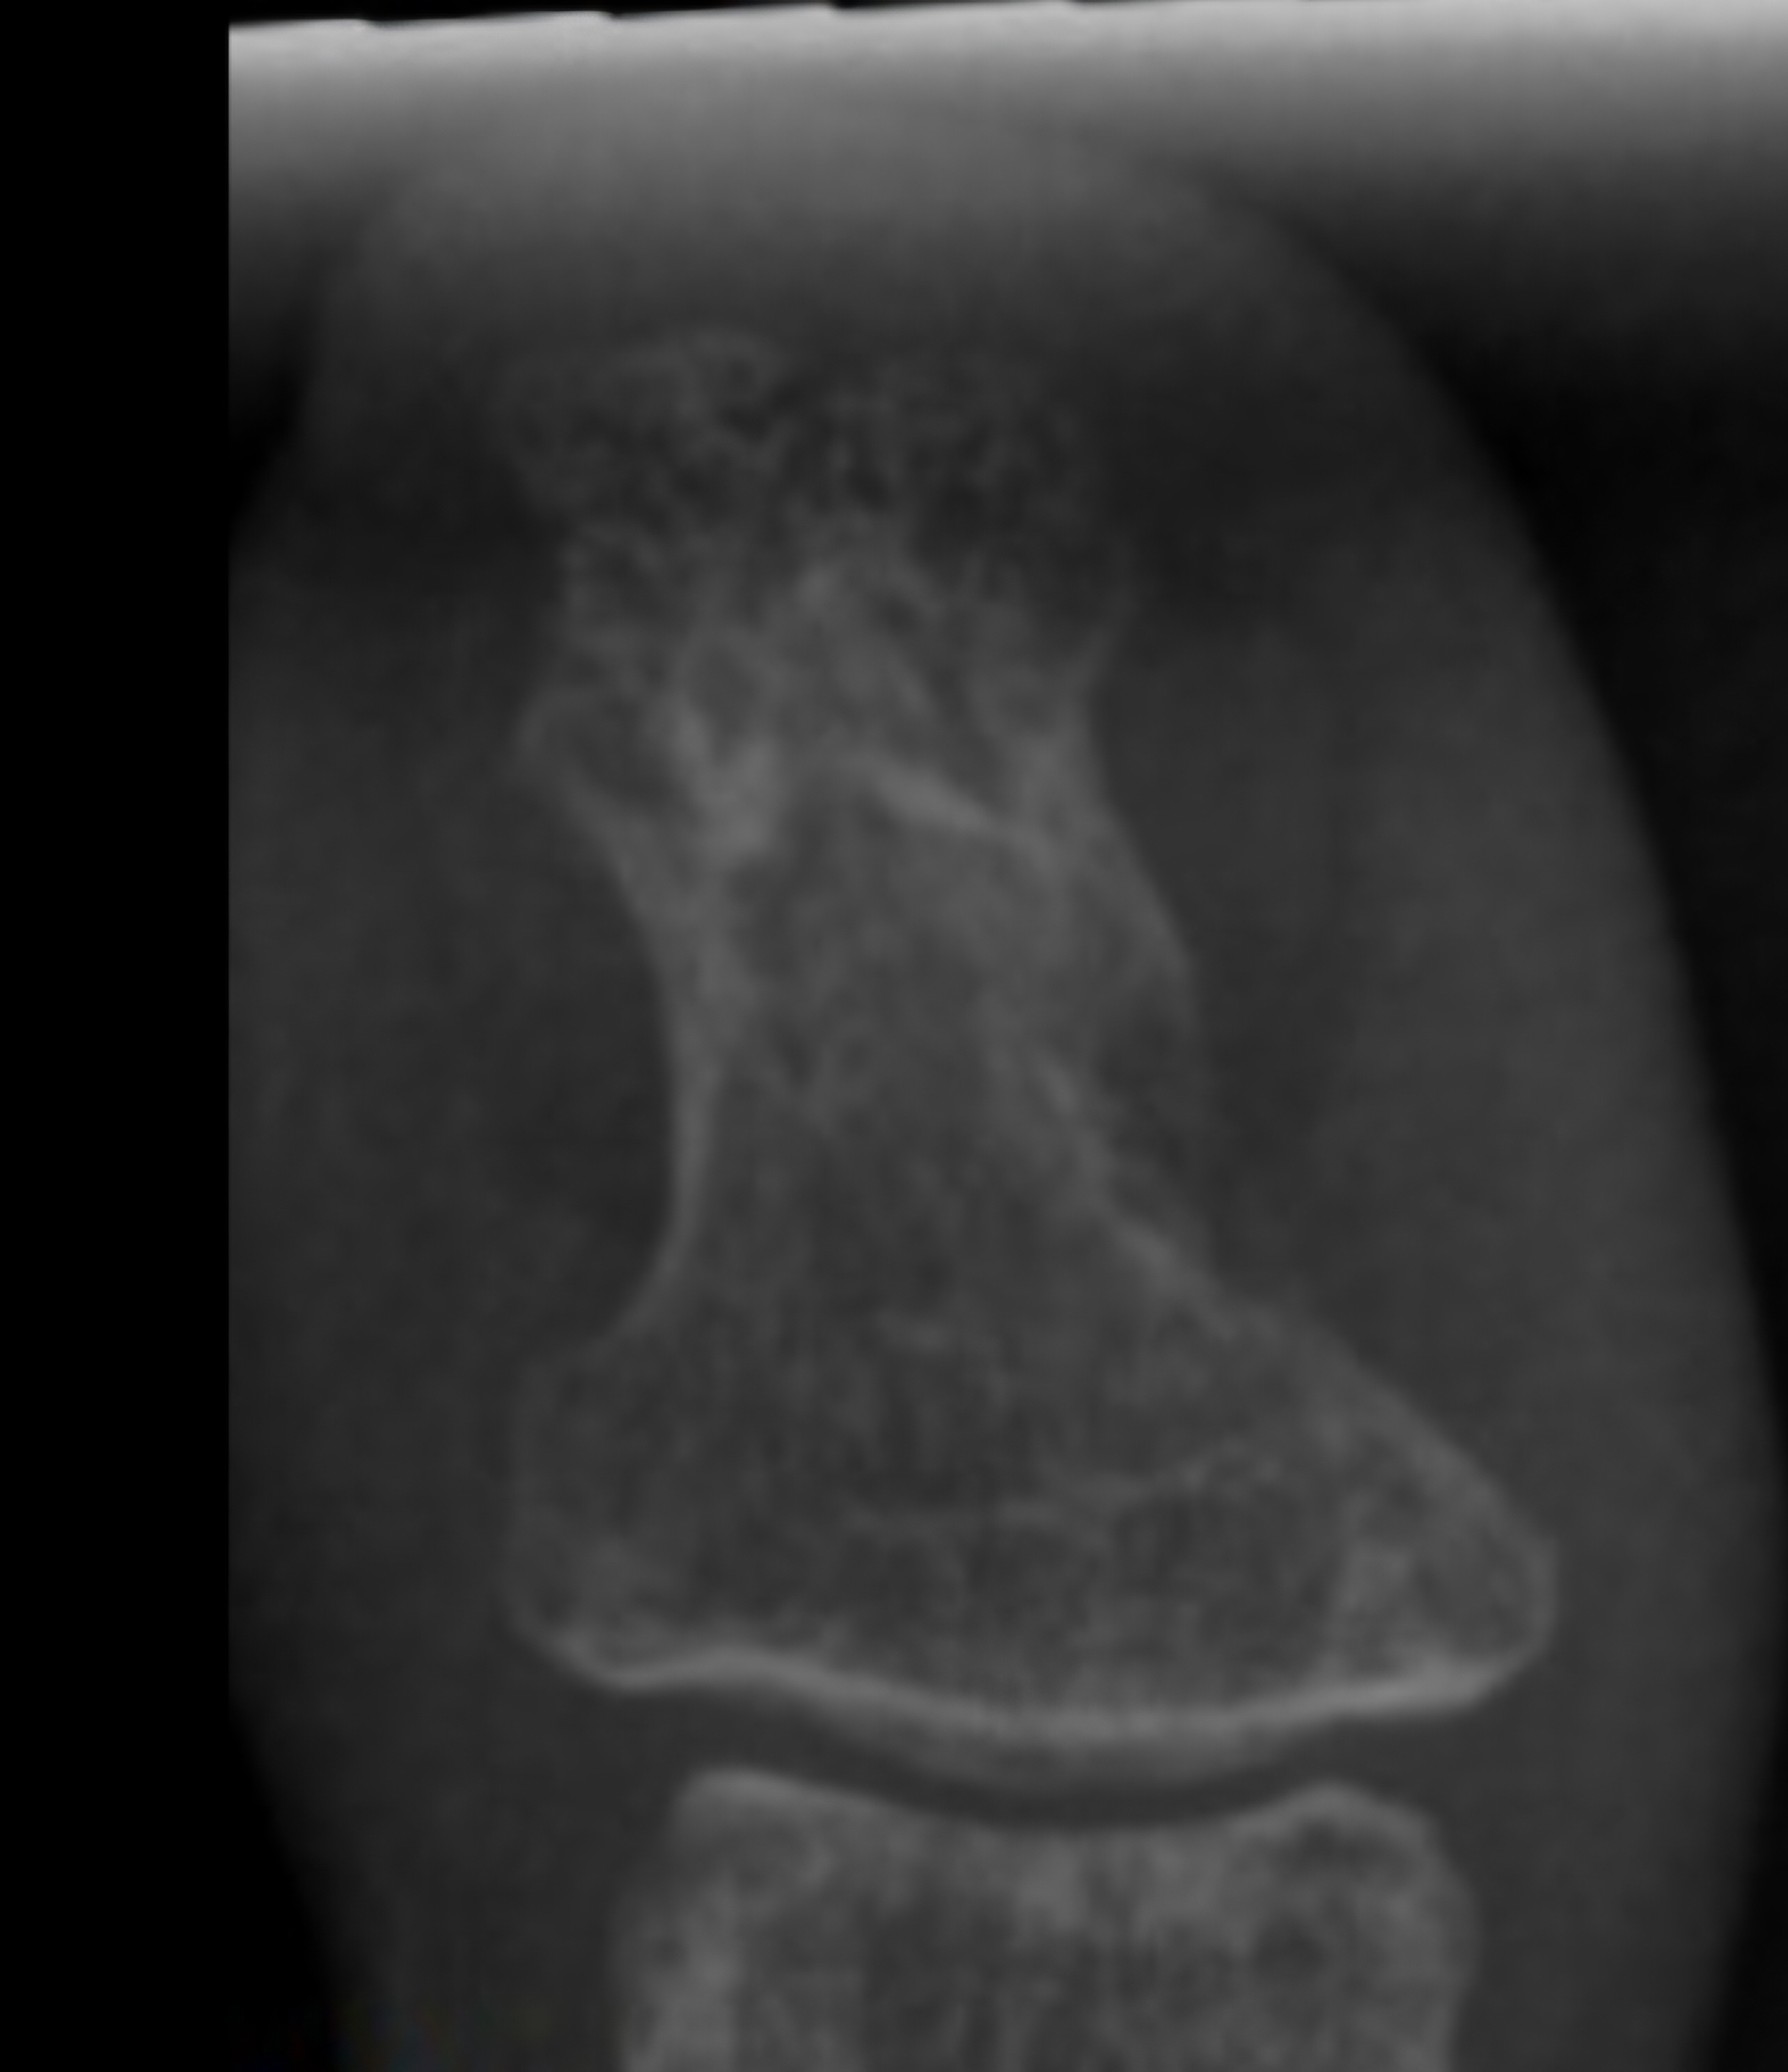

Left Great Toe 6 weeks post second bone (lateral) debridement surgery & left / right Great Toe comparisons:

Left Great Toe 12 weeks post first bone debridement surgery & left / right Great Toe comparisons:

post first bone debridement surgery (medial side)